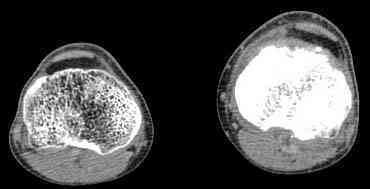

важаемые коллеги! Поступил больной 22 лет. Болен с января 2006 - появились боли в области верхнейтрети голени. При первичном осмотре в поликлинике был заподозрен первично-хронический остеомиелит - осмотрен гнойным хирургом - произведена биосия . Заключение - хондросаркома. Осмотрен онкологом - с учетом характера опухоли - химиотерапия, лучевое лечение не показано. Предложена либо ампутация, либо решение вопроса о возможности выполнения органосохраняющей операции. При обращении к нам произведена сцинтиграфия скелета - зоны гиперфиксации РФП: верхняя треть голени- 960%, нижняя треть бедра - 380%, Дистальный метафиз голени и затылочная область - 140%. В легких - метастазов нет. Произведена КТ (картинки в приложении). Учитывая абсолютную нестыковку рентгенологических и морфологических данных повторно биопсия. Выявлено, что первичная биопсия выполнялась из поверхностной параоссальной зоны - там локализованы хрящеподобные массы, далее очень плотная кость без хрящевых участков - биоптат взят фрезой с большим трудом. Морфологического заключения пока нет. Хотелось бы узнать Ваши варианты диагноза и соответственно тактику.

Не специалист по онко ортопедии, но по локализации (бедро, большеберцовая и плечевая кость), возрасть, в данный момент отсутствия метастаза и формация новой кости с мягкотканним вовлеченим, процесс больше напоминает остеосаркому большеберцовой кости.

Биопсия затрудняется из-за склероза, онко ортопеды пользуются для биопсии специальным набором режущих игл.